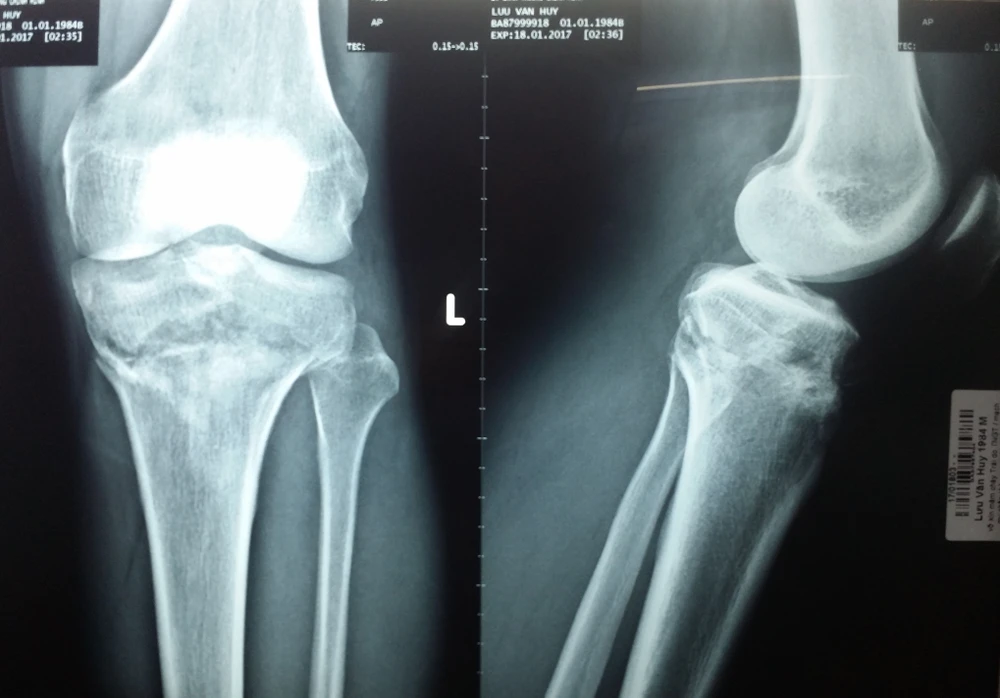

Trước đó, bệnh nhân LVH (33 tuổi, ở Long An) được một cơ sở y tế địa phương chuyển đến BV Chấn thương chỉnh hình TP.HCM với chẩn đoán gãy kín mâm chày chân trái.

Kết quả chụp X quang do cơ sở y tế địa phương thuộc tỉnh Long An thực hiện cho thấy gối-gãy mâm chày không di lệch. Ảnh: VIẾT THÔNG